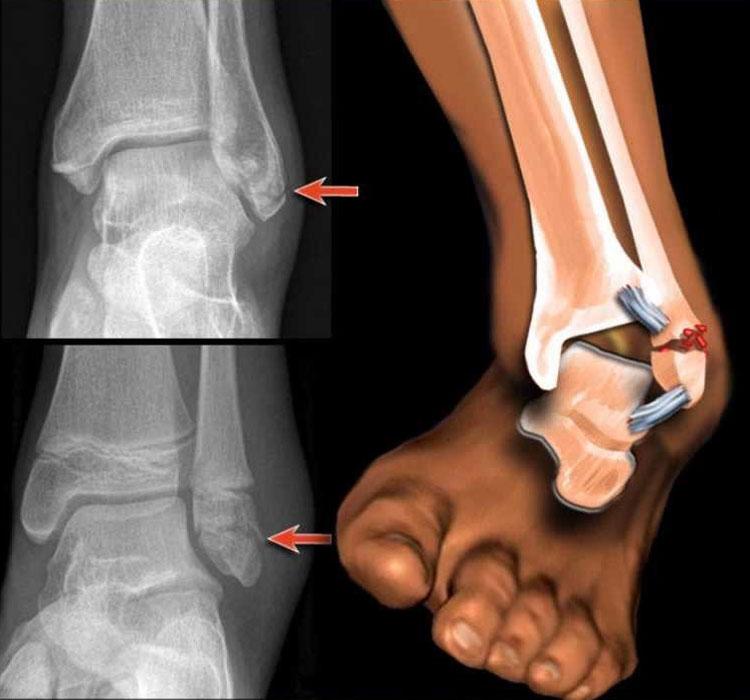

В таком положении нужно доставить больного в ближайшую больницу или травмпункт, где ему сделают рентгенографию вывихнутой конечности. Процесс заживления зависит от того, насколько быстро и профессионально была оказана как первая, так и последующая помощь.

При доставлении больного к месту лечения нужно определить, какая травма была получена. Придется дифференцировать вывих от перелома или иных поражений конечностей. Если диагноз вывих был подтверждён, надо вправить сустав. Это делает профессионал, который владеет необходимой техникой. В тяжёлых случаях ручное вправление невозможно, и применяется оперативное вмешательство – вправление хирургическим путем.

После вправления накладывается эластичный бинт или специальные перевязочные материалы, которые будут поддерживать ногу в физиологически верном положении. Суставная капсула на протяжении десяти дней, пока будет идти лечение, должна находиться в привычном положении. Так, может назначаться ношение лангета. Курс лечения зависит от особенностей травмы и степени тяжести полученного повреждения.